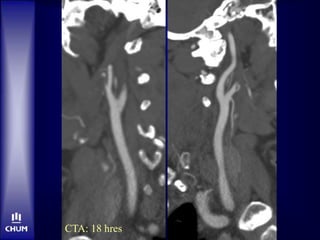

CT C- à 9h47

Bolus tPA-IV à 10h15

CTA-Source Images

CTA: 18 hres